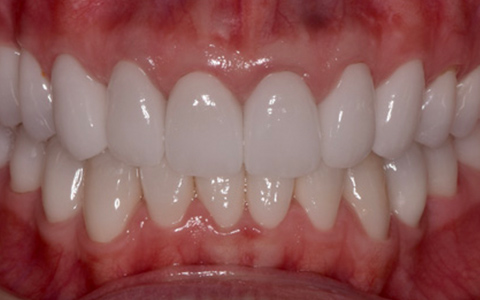

治療前

治療後

なるべく歯を残して、歯の神経も可能な限り保存し残していく方向で治療方法を検討しました。むし歯が大きく神経が侵されている歯は、抜髄を行い、精密根管治療の後にセラミックスクラウンを被せる治療方法を策定しました。患者さんのご希望と了解を得て治療を開始しました。

むし歯治療では、丁寧にむし歯だけを除去して健全な歯質だけを残します。名取歯科医院では、ラバーダムとマイクロスコープの使用が標準です。歯の根と神経の治療(根管治療)も行っていきます。

ラバーダムとはゴム製のシートで、治療する歯だけを露出させるように丁寧に切り取り、お口に装着します。唾液の中には天文学的な数の細菌が存在するため、一度治療した歯が再び悪化して再治療とならないためには、ラバーダムを装着し唾液や細菌に触れないように防湿を施した環境で治療することが何よりも大切で、歯科治療の基本です。歯の根元の黒い部分は膿の溜まった袋です。

むし歯が進行することで歯の神経まで細菌に侵されてしまった場合、昭和型の歯科治療では歯を抜いてしまう抜歯が当たり前でした。しかし、歯を抜いてしまうことで歯並びの乱れなど、ほかの歯への大きな影響があります。そこで自分の歯をできるだけ残すことを考えた「根管治療」や「保存治療」が選択されるようになってきました。

治療後の写真です。きちんと歯の根の治療(根管治療)を施すことで膿の袋も消失します。

歯ぐき(歯肉)の治療も大切です。歯ぐきを健康的な状態に治療していくことで、お口全体を審美的に優れた美しい状態に改善できます。このように歯ぐき(歯肉)の治療を行うことで、炎症を抑え、健康な状態をつくることができます。歯ぐきのコンディションを回復させると同時に、仮歯を入れます。しかしこれは治療中の隙間を埋めたり見た目を取り繕う「仮歯」とは異なります。プロビジョナルレストレーションと言い、最終的な歯(本歯)と同じ形体をもつ歯で、治療した歯や周囲の歯、反対側の歯、歯ぐきなどお口全体の回復と調和を整える大切な治療プロセスです。もちろんこの期間に仮歯での噛み合わせ、咀嚼や嚥下、または発音や発語など機能的な回復に不具合がないか、顎関節への影響や負担がないか検証する期間でもあります。

仮歯で機能回復の確認を行い、そしてさらに微調整を行います。機能的・審美的に改善を確認できた仮歯の形態を元にセラミックスクラウンを作製します。熟練した歯科技工士によるセラミックス制作を行い、装着後に最終的な微調整(咬合調整)を施し、むし歯治療、歯の根の神経治療(根管治療)、白いセラミックスによる修復治療のすべてが終了しました。

| 費用 | ジルコニアセラミック24本:5,280,000円 根管治療(小臼歯5本):770,000円 根管治療(前歯6本):792,000円 合計:6,842,000円 |

| リスク・副作用 | 治療中に一時的な咬合痛や冷温水痛、若干の歯肉の腫れ、発赤などを生じることがあります。また仮歯の時期には仮歯の脱離や破損の可能性、舌感などに違和感を覚えることがありますが、本歯に移行するまでに通常消失します。 ※すべて症例による違いや個人差があります。 |

※表示金額は全て税込みです。